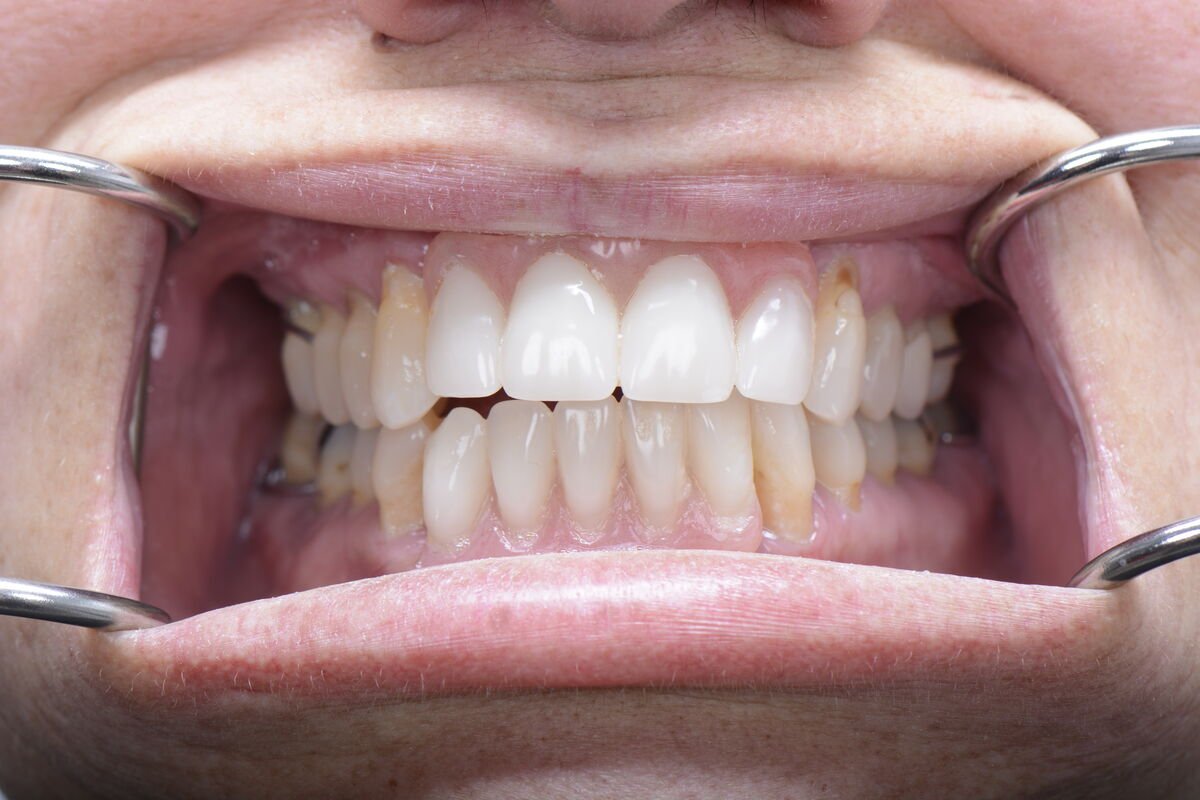

Real Smile Transformations

See the life-changing results from real patients who chose Fusion Dental Implants.

Our practice is built around the full arch restoration, including All-on-4, All-on-6, and zygomatic implant procedures. These treatments replace an entire arch of missing or failing teeth with a fixed, permanent set of new teeth supported by as few as four dental implants. Many of our patients receive temporary teeth on the same day as their surgery, leaving our office with a complete smile.